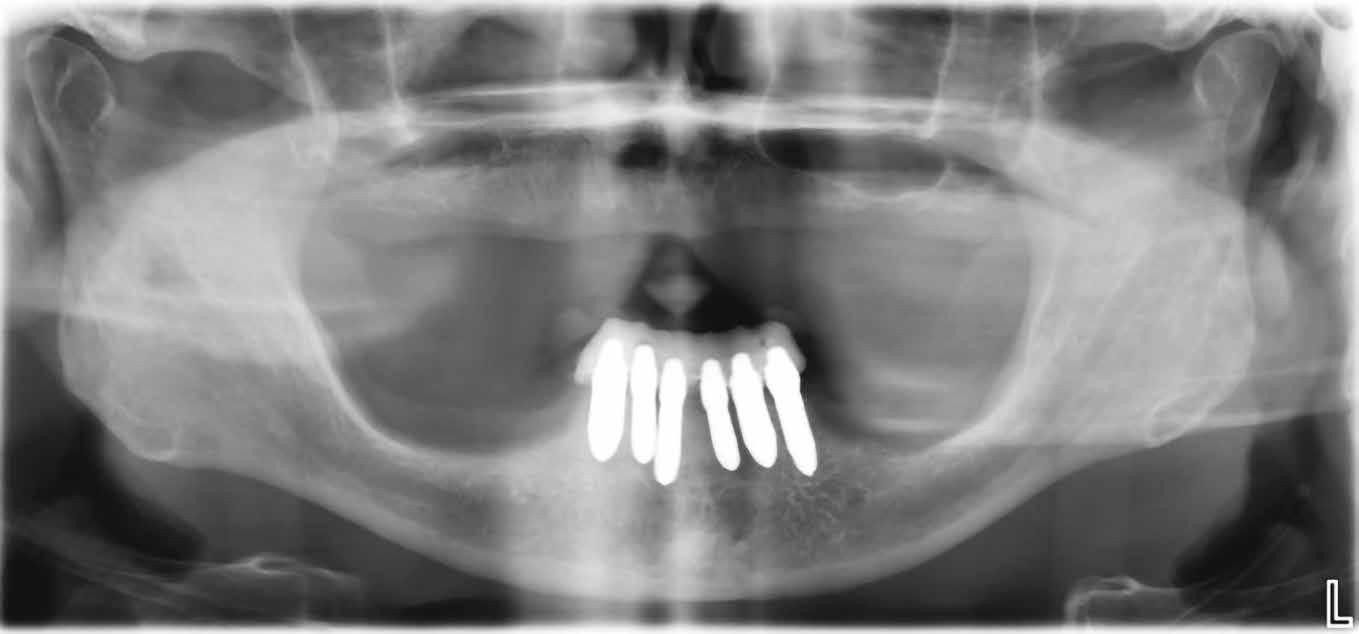

A 75 éves páciens új fogsorokat szeretett volna. Felül nem kielégítő teljes lemezes kivehető fogsora volt, alul pedig szintén nem megfelelő részleges fogsora, néhány devitális, apikális oszteolízist és masszív szekunderkárieszt felmutató mutató maradék frontfogon. Az endodonciai beavatkozást a páciens elutasította. Ehelyett kerámiaimplantátumokra alapozott kezelést kívánt. Az úr általános egészségi állapotában panaszok mutatkoztak. A CMD-index nem volt számottevő. A DVT-vizsgálat (1. kép) alapján megállapítható a 42-es fog decens apikális oszteolízise, számottevő vertikális és horizontális csontveszteség a rágóterületen, valamint az

1. kép: Kiindulási helyzet: az OPG hat devitalizált alsó frontfogat ábrázol, részleges apikális oszteolízissel, szekunderkáriesszel, horizontális csontfelszívódással a rágóterületen.

FDOK/NICO értelmében HU alapján mért erőteljes csontsűrűség-csökkenés mutatkozik az 18, 17, 13, 23, 27 és 28 fogak régiójában.